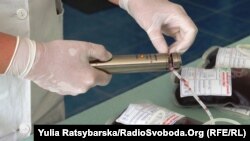

14 червня – Всесвітній день донора крові. За статистикою, один донор крові може врятувати життя трьох людей. Проте існує лише кілька десятків країн, де донорська кров забезпечує 100% потреби, необхідної для населення. В Україні показники донорства крові невисокі. За словами експертів, серед головних чинників такої ситуації – недовіра до лікарень, відсутність належної техніки, а також менталітет. В Україні не допомагає залученню до донорства навіть оплата за здачу крові і два вихідних. Цікаво, що в багатьох країнах світу стати донором – це звичайна справа. Не за гроші! Радіо Свобода поцікавилося, як та чому стають донорами в інших державах?